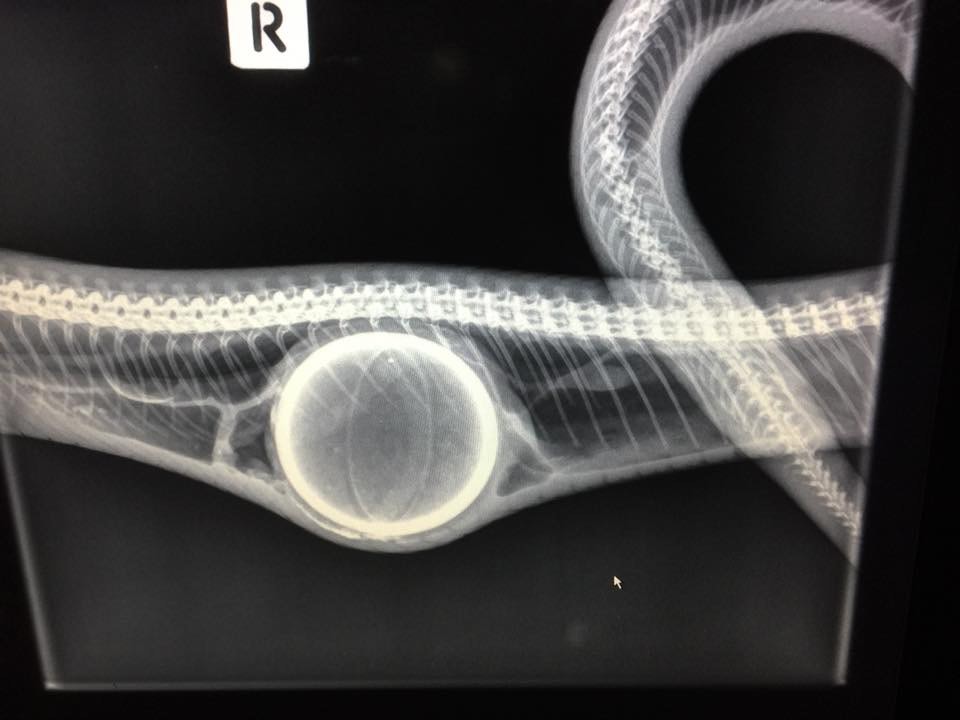

An X-ray revealed the snake had chowed down on a tennis ball.

A coastal carpet python was found in Queensland, Australia, with a tennis ball in its gut.